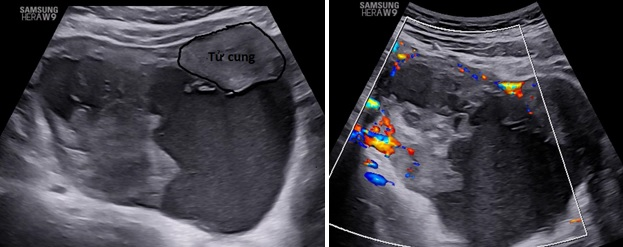

– Siêu âm: Tử cung và buồng trứng (T) bình thường, buồng trứng (P) không quan sát thấy. Từ cùng đồ sau lan qua hố chậu (P) có 1 khối echo hỗn hợp không đồng nhất, kích thước# 105x 98x 59 mm, bên trong có nhiều mảng echo dày bờ không đều, di động khi di chuyển đầu dò, có tăng sinh mạch máu mức độ 3 Ở ngoại vi khối này có hình ảnh mô buồng trứng bình thường. Dịch cùng đồ# 8 mm.

– Chẩn đoán siêu âm: Theo dõi khối huyết tụ thành nang (HTTN) chưa loại trừ khả năng: u đơn thùy buồng trứng (P) có mảng xuất huyết bên trong.

Hình 1: Mặt cắt ngang qua bụng trên thang xám và Doppler, khối u nằm sau tử cung lệch qua hố chậu phải có khối phản âm hỗn hợp không đồng nhất, có tăng sinh mạch máu ngoại vi